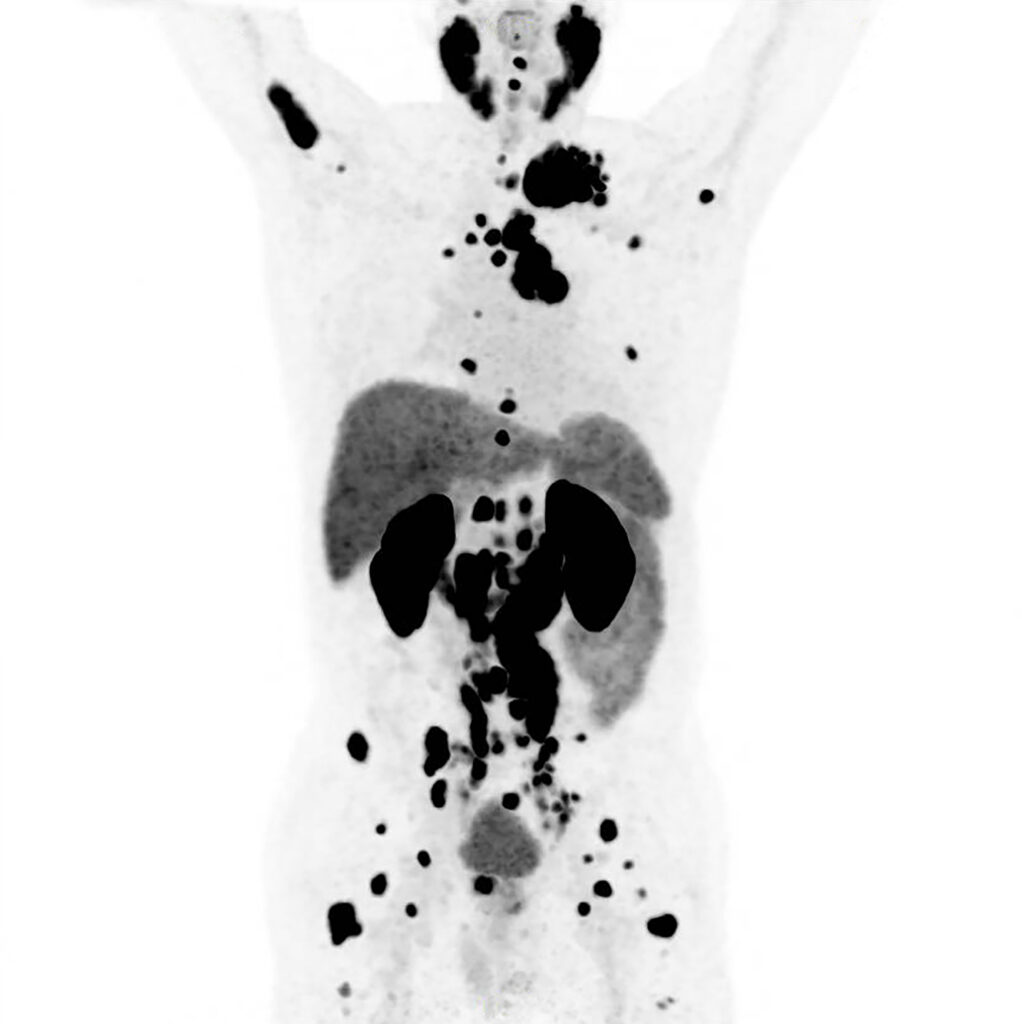

Am Freitag erwartete mich eine PET-CT-Untersuchung. Ich wollte ja schon immer mal auch von innen heraus strahlen. Ich sollte eine schwach radioaktive Flüssigkeit in die Armvene injiziert bekommen, damit sich das markierte Medikament in Geweben mit hoher Stoffwechselaktivität anreichert – wie beispielsweise in Tumoren – und so eine präzise Lokalisierung der Befunde ermöglicht.

Die PET-CT verlief problemlos und nach 30 Minuten durfte ich mich wieder ankleiden. Die Daten würden direkt an die Klinik übermittelt und die Mitarbeiterin wünschte mir aufrichtig viel Erfolg bei meiner Behandlung. Damit hatte ich die vorerst letzte Untersuchung hinter mich gebracht. Am Montag stand das Abschlussgespräch in der Klinik an. Nun hatte ich das Wochenende, um mich ein wenig von den physischen und psychischen Strapazen der letzten zwei Wochen zu erholen. Meine Tankfüllung blinkte bereits auf Reserve.

Ich wollte endlich mal Ordnung in den Papierstapel aus Befunden, Analysen und Rechnungen bringen. Der Bürokrat in mir bat um Aufmerksamkeit. Dabei fiel mir auch der Befund der PET-CT-Untersuchung in die Hände. Diesem hatte ich bis dato noch keine Aufmerksamkeit geschenkt. Mit meinem medizinischen Duolingo-Wortschatz kam ich allerdings nicht weiter und bat schwachsinnigerweise ChatGPT um Unterstützung. Hätte ich wohl besser bleiben lassen.